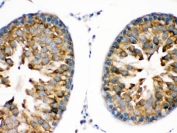

IHC testing of FFPE rat testis with TRPM5 antibody. HIER: Boil the paraffin sections in pH 6, 10mM citrate buffer for 20 minutes and allow to cool prior to staining.